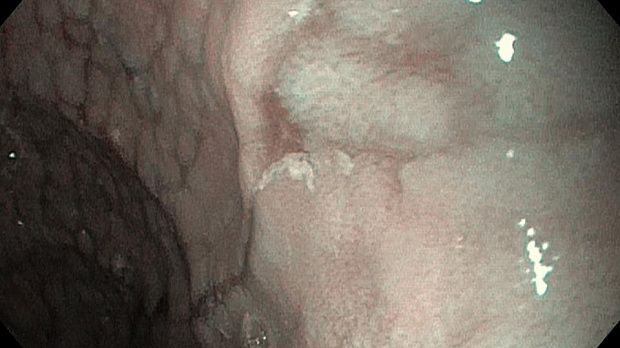

Публикации из социальных сетей: “Cobblestone esophagitis” (эзофагит со слизистой булыжной мостовой)

“Cobblestone esophagitis” (эзофагит со слизистой булыжной мостовой) - редкая эндоскопическая находка и ассоциируется с эозинофильным эзофагитом, кандидозом и пищеводом Барретта у взрослых. Он также может быть найден при тяжелом рефлюкс-эзофагите, вторичен к дистальной обструкции гастроинтестинального тракта. В нашем случае - это пациент после с 9-летним стажем бандажирования кардиального отдела желудка, признаками дуоденостаза, фундальной эрозивной гастропатией, расширением пищевода и уровнем жидкости в нем при горизонтальном положении, грыжи ПОД, эрозивно-язвенном дистальном эзофагите.. Пациент просто пришел удалить полип в прямой кишке и заодно посмотреть, что творится в желудке.... Ацетообеление+NBI+биопсия. ИПП на 3-4 мес и повтор для решения о Барретте.